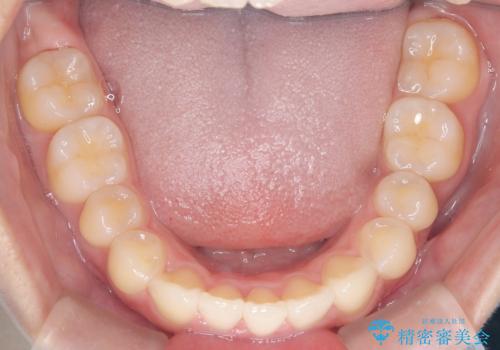

【インビザライン】前歯を下げたい。

- 前歯が出ていることを主訴に来院されました。

下顎前歯が1本欠損していることもあり、前突はある程度残ることを説明し、インビザラインにて治療を行いました。

今回は抜歯矯正ではなく歯列弓の拡大とIPR、遠心移動を行って配列することができました。

口元も改善し患者さんには喜んでいただけました。

下顎前歯が1本少ないため、上下の正中は合いません。